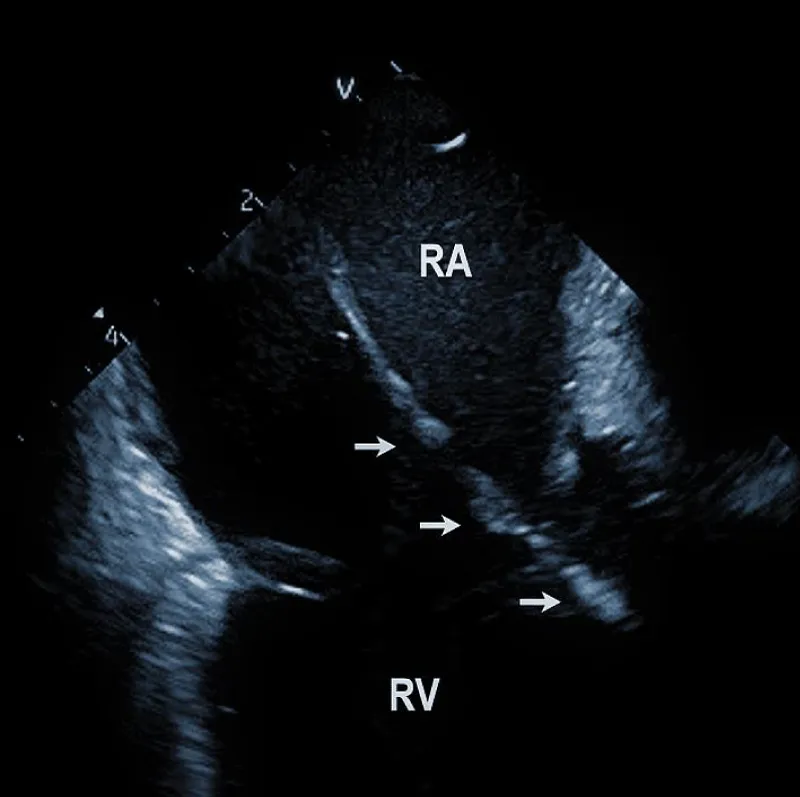

Lead adherent echo densities (LAE): ICE allows visuali-zation of the leads and echo densities adherent to them. In our experience, LAE can be detected in the majority of patients (Figure 2A). One recent study revealed LAE in 72% of cases [10]. Locations of LAE were the superior vena cava (16%), its junction with the right atrium (11%), right atrium (57%), and tricuspid annulus (16%). Finding LAE opens the question of their clinical importance. Interestingly, Ho, et al. systematically performed TEE before TLE, which was performed for non-infectious indications in 108 consecutive patients [11]. The authors reported an 18.5% incidence of lead thrombi, all of which were < 2 cm. This figure is significantly less than in the above study. This discrepancy can be explained by the higher resolution and superior maneuverability of ICE compared to TEE [12].

Figure 2A: Depiction of the lead adherent echodensity (arrows) floating on the ICD lead in the right ventricle (RV).

Therefore, ICE could be essential in patients with a suspected diagnosis of infective endocarditis since it necessitates the removal of the entire pacemaker or ICD system. Narducci et compared ICE with TEE to detect TLE in the setting-related infective endocarditis [13]. ICE identified the presence of intracardiac masses in all 58 patients (100%), whereas TEE identified the presence of ICM in only 38 patients (65%). The authors concluded that ICE is a useful technique for diagnosing intracardiac masses, thus providing improved imaging of right-sided leads and increasing the diagnostic yield compared with TEE. The pretest probability of infective endocarditis determines the incremental diagnostic value of ICE in infection of implantable devices. If the diagnosis of endocarditis is clinically rejected, even ICE does not improve the clinical decision-making process. The best diagnostic value of ICE was found in patients with a probable diagnosis of endocarditis. We recently had an ongoing pilot project focused on biopsies from TLE using a bioptome and ICE guidance. In anecdotal cases, it helped to establish the diagnosis of infective endocarditis.

Technically speaking, the presence and size of intracardiac masses in patients suspected of infective endocarditis are critical in planning TLE procedure (Figure 2B). Large vegetations were found more common in patients with renal failure, heart failure, ICD system, and loops of the leads [14]. In another study, diabetes was related to larger vegetations, similarly younger age. Anticoagulation therapy resulted in smaller vegetations [15].

Figure 2B: Large vegetation floating on the ICD lead in the Right Atrium (RA). RV: Right Ventricle.